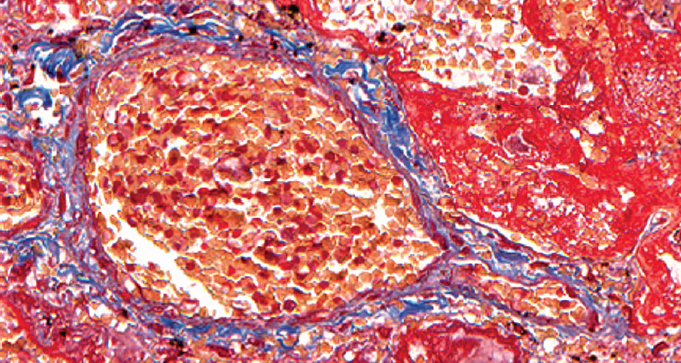

При патологоанатомическом исследовании — ткань легких с диффузными ателектазами, чередующимися с небольшими эмфизематозно расширенными участками, мелкоочаговыми кровоизлияниями в расширенные межальвеолярные перегородки (рис. 1). Большая часть альвеол звездчатой формы, очагово заполнены серозно-фибринозным экссудатом (рис. 2), слущенными альвеолоцитами, альвеолярными макрофагами (рис. 3). Часть альвеол выстлана гиалиновыми мембранами (рис. 4). Сосуды микроциркуляторного русла, расположенные в межальвеолярных перегородках, округлой формы, в просвете большей части которых определяются нити фибрина. Эндотелиальные клетки, выстилающие сосуды, набухшие, овальной формы, другие — более вытянутые, сохраненные не на всем протяжении стенки сосуда. Бронхи среднего и более крупного калибра звездчатой формы, стенка преимущественно утолщена за счет отека и склероза подслизистого слоя. Слизистая оболочка бронхов представлена цилиндрическим эпителием с дистрофическими изменениями, местами слущенным, в сохраненных участках с явлением пролиферации. В просвете бронхиол и более крупных бронхов выявляются десквамированный эпителий, единичные эритроциты, макрофаги. Кроме этого, преимущественно перибронхиально — диффузная лимфоцитарная инфильтрация с примесью умеренного количества нейтрофильных лейкоцитов; разрастание соединительной ткани, образование мелких единичных лимфоидных фолликулов.

Рис. 4. Часть альвеол выстлана гиалиновыми мембранами. Окраска по Массону (трихром). Ув. ×300 / Fig. 4. Part of the alveoli is lined with hyaline membranes. Masson coloring (trichrome). Magnification ×300